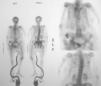

Masa glútea en anciana con enfermedad de Paget del hueso

A. Ballarín González, P. Laguna del Estal, H. de la Torre Martí, J.M. Palau Fayos

Servicio de Medicina Interna. Hospital Universitario Puerta de Hierro. Madrid. España